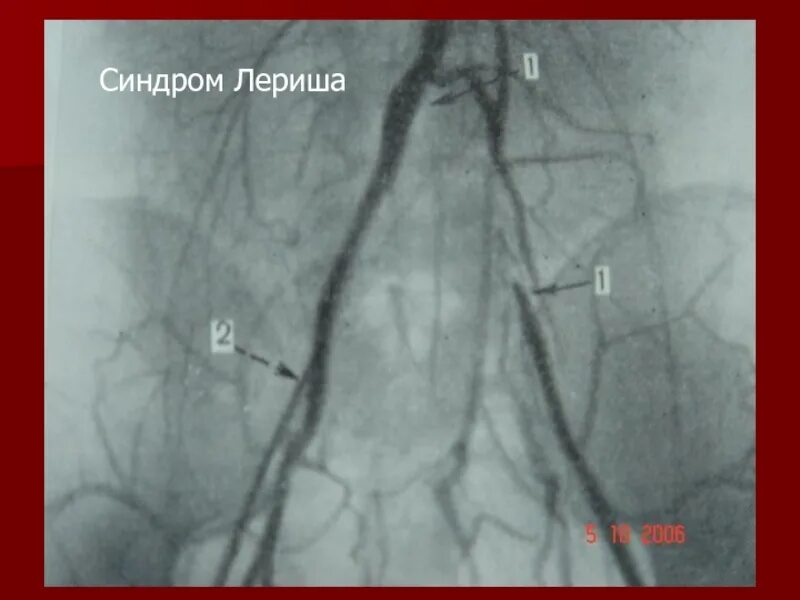

Атеросклероз аорты и ее ветвей